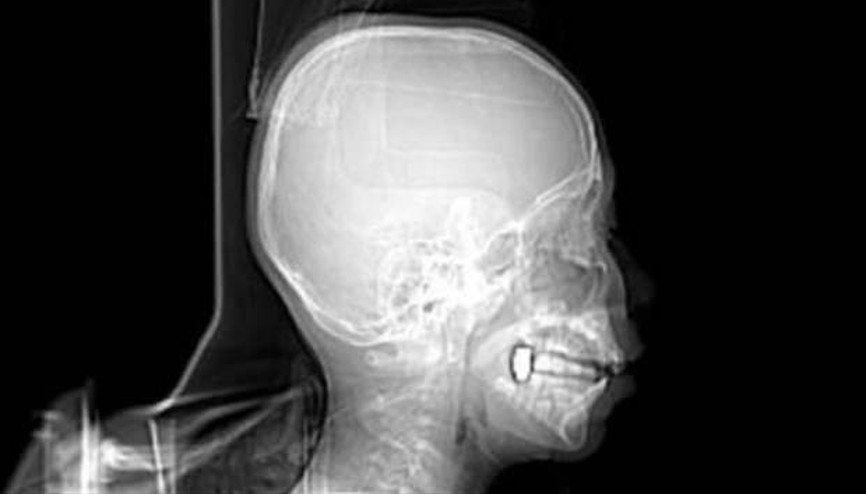

#Çene YapısıKONYA’da sokak çeşmesinde halı yıkayan annesine yardım ederken başına mermi isabet ettiği ortaya çıkan Osman Gündüz’ün (9) çenesine saplanan mermi çekirdeği, yapılan ameliyatla çıkarıldı. Mermi, balistik raporu alınması için polise teslim edildi. Polis ekiplerinin çalışmaları sürüyor.